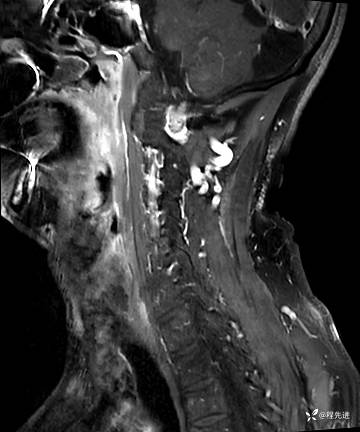

MRI平扫+增强:

T2压脂: